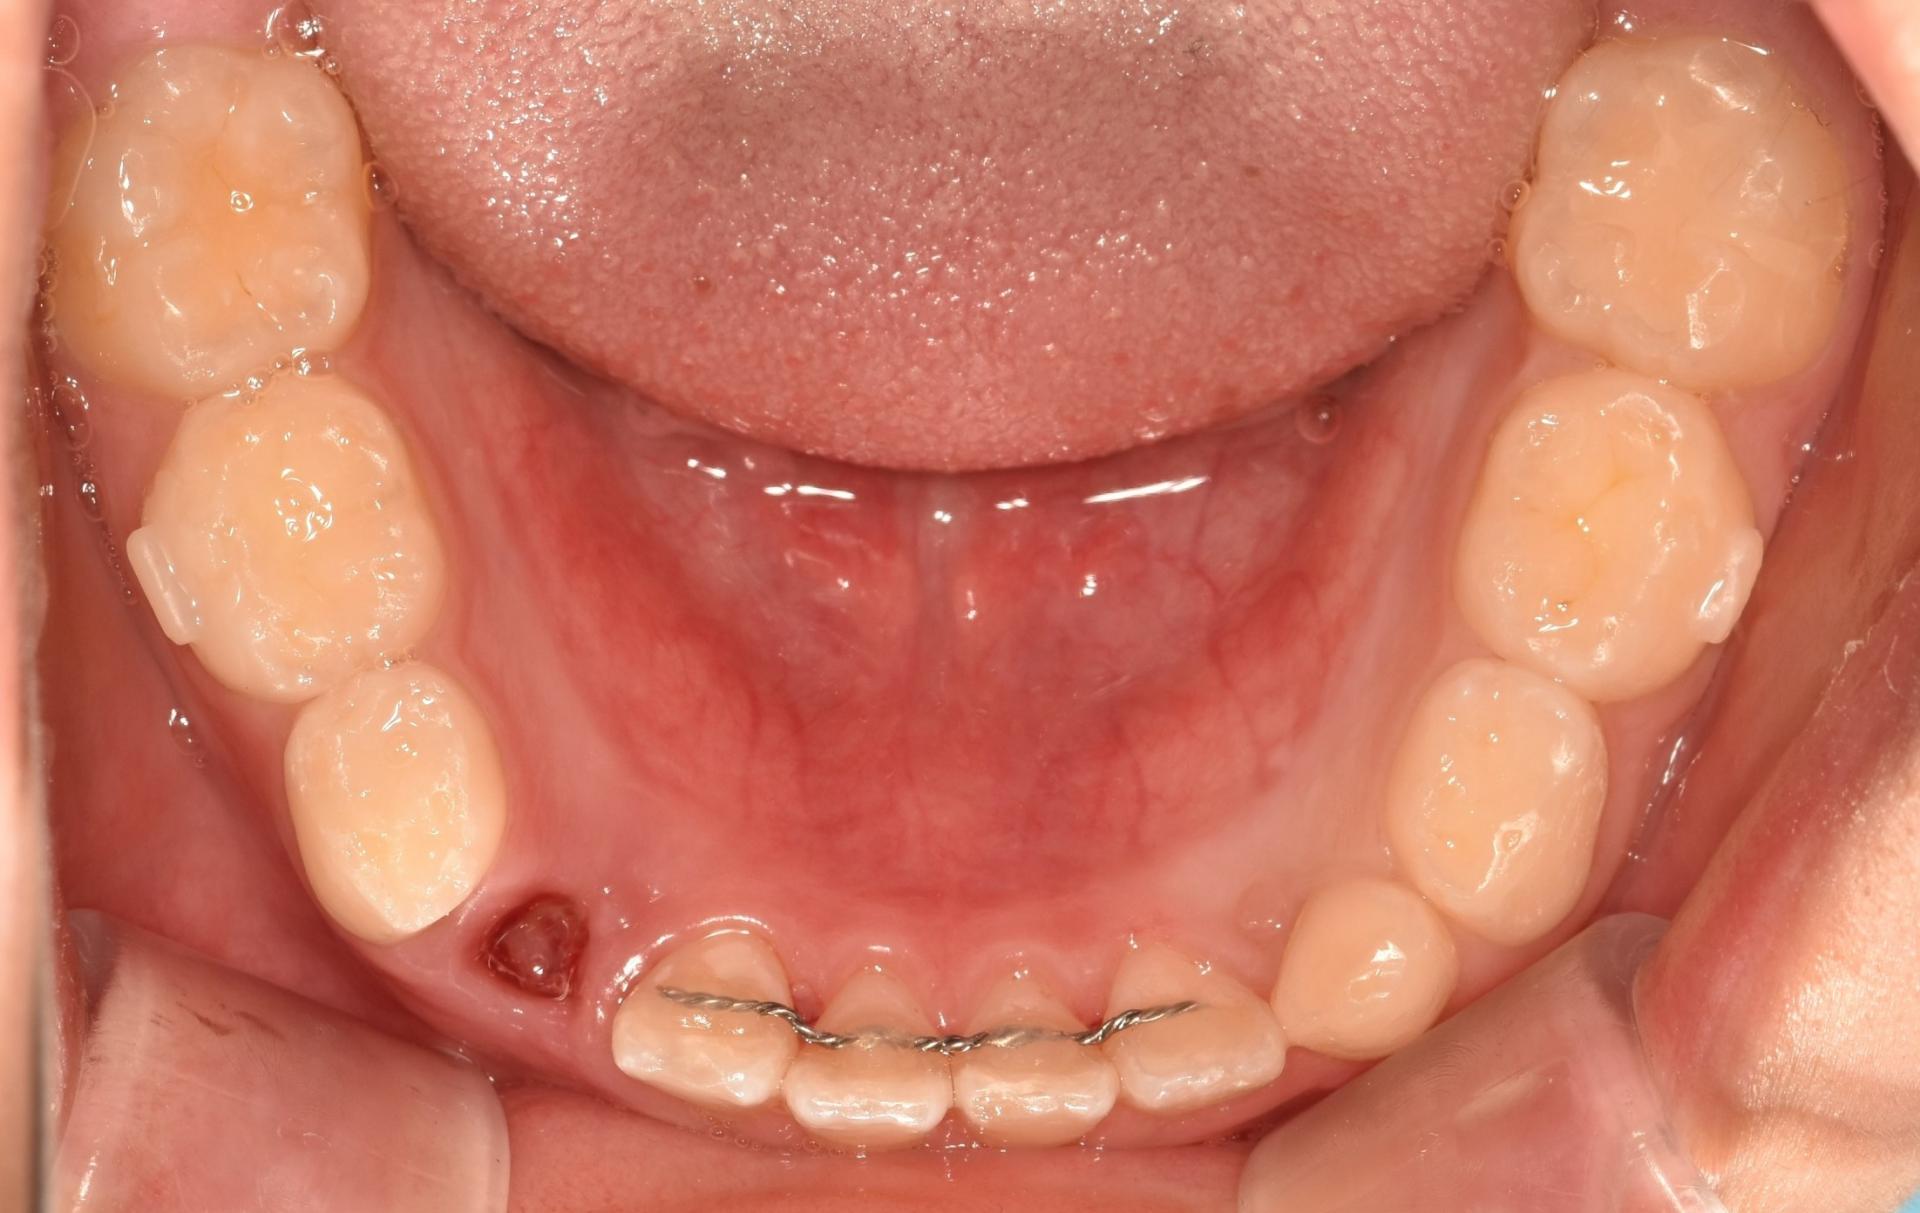

교정 진행중, 투명교정장치를 착용한 모습입니다. 치아위로 철사가 지나가지 않으니, 교정하는 것이 남들 눈에 띄지 않게, 편하게 뺏다 꼈다 하고, 철사 찔림이 발생하지 않으며 통증없이 치료를 진행할 수 있다는 장점이 있어 많은 어린이들이 선호하는 치료입니다!